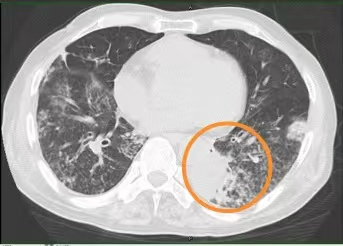

没想到2个月前,王大爷突然开始喘息、气促、胸闷,甚至走几步路都觉得很累,不得不停下休息,慢慢地生活不能自理,连吃饭也没胃口,体重下降。3周前咳嗽、咯痰更重了,咯的全是黄稠痰。在当地医院住院,胸部CT提示:左肺下叶炎症并部分肺实变、右肺中叶部分支气管扩张,经抗感染、吸氧等治疗后一点没缓解。

入院后,医生给王大爷用了抗感染、止咳化痰、营养支持等治疗,可3天过去,王大爷喘息、气促、咳嗽、咯黄痰仍没缓解,胸壁包块也没缩小,包块局部触摸还有波动感。复查胸部CT提示:双肺多发结节影、磨玻璃影、斑片影,部分见肺实变影,部分支气管牵拉扩张,左肺下叶部分支气管闭塞。